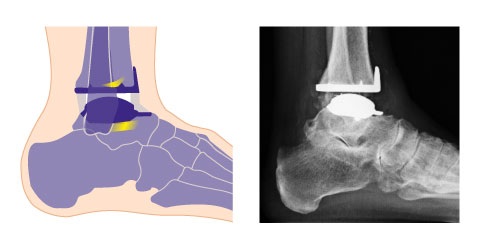

Darstellung von individualisierten Sprunggelenksprothesen. Sowohl die 3-Komponenten-Prothese als auch die 2-Komponentenprothese besteht aus einer Schienbein- und einer Sprungbeinkomponente. Bei der 2-Komponenten-Prothese (unten) ist das Inlay am Schienbein fixiert. Die 3-Komponenten-Prothese (oben) verfügt dagegen über ein mobiles Inlay, das als 3. Komponente angesehen wird.

Heute werden häufig knochensparende Sprunggelenkprothesen (OSG-TEP) aus drei Komponenten verwendet. Das Schienbeinimplantat (oben, violett), das Kunststoffinlay (weiß) und das Sprungbeinimplantat (unten, violett) sind zueinander beweglich. © Gelenk-Klinik

Die knochensparenden 3-Komponenten-Prothesen für das obere Sprunggelenk (OSG-TEP) bestehen aus mehreren Komponenten. Die Teile der Sprunggelenksprothese stehen frei übereinander, sind zueinander beweglich und überdecken die geschädigten Gelenkabschnitte (blau). Die Implantate wachsen an den Gelenkflächen in die Knochenoberfläche ein. Geführt werden die Anteile der Sprunggelenksprothese von den vorhandenen Sehnen, Muskeln und Bändern. Eine intakte Beinachse sowie optimale Fußstellung und funktionierende Bänder sind unverzichtbar für eine haltbare Sprunggelenksprothese. © Gelenk-Klinik

Bei den individualisierten TEP (Totalendoprothesen) für das Sprunggelenk werden sowohl das Sprungbein (Talus) als auch die Schienbeingelenkfläche (Tibiagelenkfläche) mit einer Metallkappe überzogen. Die Rückflächen der Kappen sind titanbestrahlt und mit Hydroxylapatit beschichtet und gehen während des Heilungsprozesses eine stabilen Verbindung mit dem natürliche Knochen ein.

Die dritte Komponente der Prothese ist ein frei beweglicher Polyethylen-Gleitkern, der die wichtige Bewegung zwischen den beiden Gelenkpartnern vermittelt. Die freie Beweglichkeit des Gleitkernes ermöglicht eine uneingeschränkte Belastung der Prothesenflächen. Die Kunststoffkerne wurden in den letzten Jahren optimiert. Sie sind härter und bewirken eine bessere Quervernetzung des Polyethylens.

2-Komponenten-Sprunggelenksprothese mit fixiertem Inlay links. Rechts ist die 3-Komponenten-Sprunggelenksprothese abgebildet. Sie besitzt mit dem mobilem Inlay zusätzlich zur Schienbein- und Sprungbeinkomponente eine eigenständige dritte Komponente.

Schema und Röntgenaufnahme einer individualisierten Sprunggelenksprothese. Die Überkronung der belasteten Gelenkflächen von Schienbein (Tibia) und Sprungbein (Talus) reduziert die Gelenkschmerzen. Das bewegliche Inlay aus Polyethylen zwischen den Komponenten vermindert die Belastung der Knochenanteile unter der Prothesenfläche. Die Kraft wird in jeder Fußstellung gleichmäßig übertragen. © Gelenk-Klinik